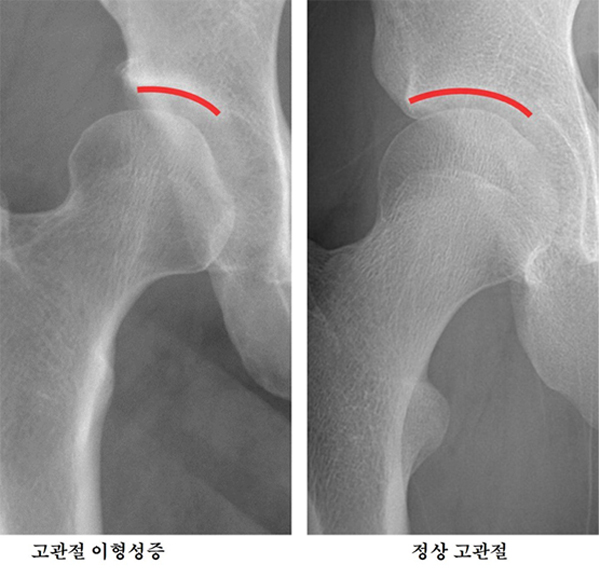

[제주, 제주인의 건강보고서 Ⅷ 건강다이어리] (158)대퇴골두 무혈성 괴사